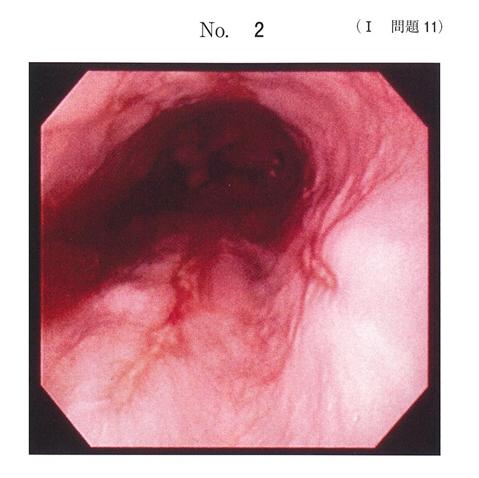

粘膜が瘤状に隆起していまして、これが食道全周性に認められます。粘膜表面の性状には異常を認めません。

みたいなのでどうでしょう?